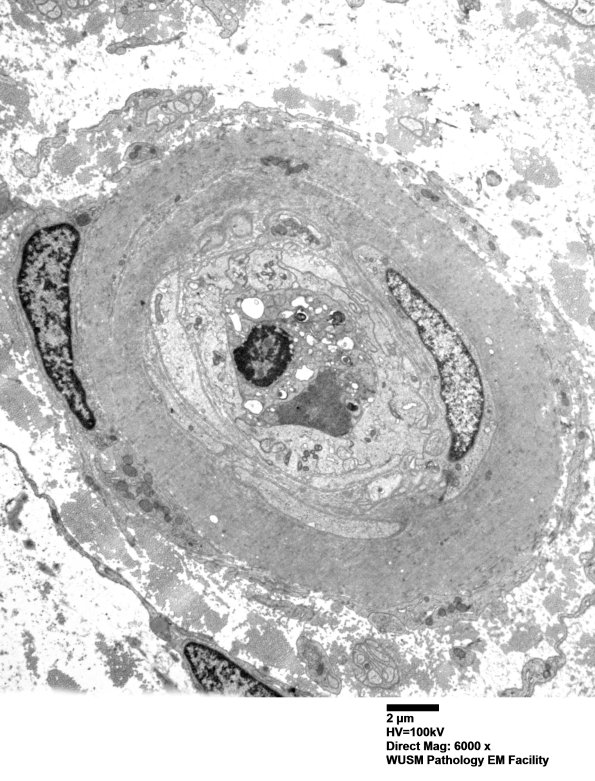

5C4,5 This vessel shows purely collagenous thickening of the endothelium. (electron micrographs)